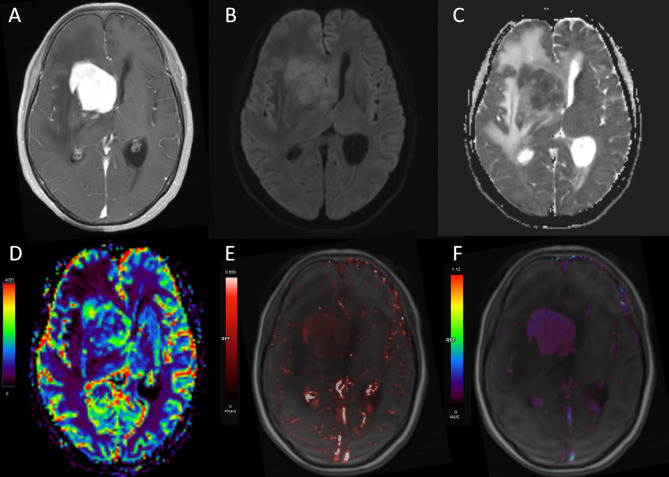

Purpose: The differential diagnosis of primary central nervous system lymphoma (PCNSL) and atypical glioblastoma (aGBM) exhibiting homogeneous enhancement and negligible necrosis poses a significant challenge for conventional MRI. The study aims to investigate diffusion-weighted imaging (DWI), dynamic contrast-enhanced (DCE) MRI, and contrast agent (CA) preload dynamic susceptibility contrast perfusion-weighted imaging (DSC-PWI) to differentiate aGBM and PCNSL.

Materials and methods: This retrospective study analyzed 27 patients with aGBM (solid enhancement without visible necrosis) and 105 patients with PCNSL, all undergoing preoperative DWI, DCE-MRI, and CA preload DSC-PWI. The relative apparent diffusion coefficient (rADC) and relative cerebral blood volume (rCBV) were obtained from DWI and DSC-PWI. The pharmacokinetic parameters (Ktrans, Ve, Kep, and iAUC) were acquired using DCE-MRI. The independent-samples t-test and Mann-Whitney U test were utilized to compare parameters. A binary logistic regression analysis was performed to assess the combined effect of various parameters. Before regression analysis, collinearity analysis of parameters was performed. The diagnostic capability of each parameter and their combination were evaluated by receiver operating characteristic (ROC) with area under the curve (AUC) and compared with DeLong test.

Results: In comparison to aGBM, the Ktrans, Ve, and iAUC were significantly elevated in PCNSL, whereas the rCBV and rADC were significantly lower (p < 0.05 for all comparisons). Meanwhile, these parameters allowed excellent diagnostic performance (AUC = 0.817 [rCBV], 0.751 [rADC], 0.808 [Ktrans], 0.765 [Ve], and 0.801 [iAUC]; DeLong test, p > 0.05 for all comparisons). Notably, the combination of all these parameters significantly increased the probability of distinguishing aGBM from PCNSL (AUC = 0.966).

Conclusions: DWI, DCE-MRI, and CA preload DSC-PWI can effectively differentiate aGBM from PCNSL, and the combination of all three techniques significantly enhances the discriminatory efficacy.